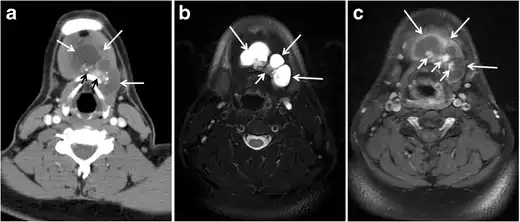

Fig. 6. A 61-year-old female patient with locally aggressive PTC. an Enhanced axial CT scan of the neck demonstrates a heterogeneous infiltrative thyroid mass. This mass diffusely involves the entire gland and circumferentially encases the trachea with involvement of bilateral tracheoesophageal grooves (white arrows). b, c Additional axial cranial images show right cricoid cartilage destruction (black arrows in b), right thyroid cartilage destruction (black arrow in c), right vocal cord paralysis (white arrows in b), and bilateral cervical lymphadenopathy (arrowheads).[1]